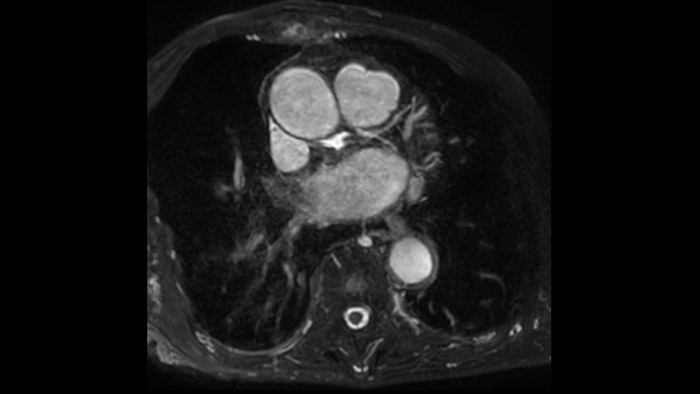

IntelliSpace Portal MR Caas5,6 4D Flow post-processing solution enables generation of 3D volume reconstructions, to visualise and evaluate blood flow in cardiovascular structures, including heart valves, chambers, and vessels, based on cardiovascular MR 4D Flow imaging.

IntelliSpace Portal offers a Comprehensive Cardiac MRI Suite, providing dedicated workflows for functional analysis, viability, LGE, cardiac mapping assessment and RV/LV functional analysis in less than 5 min. per case1.